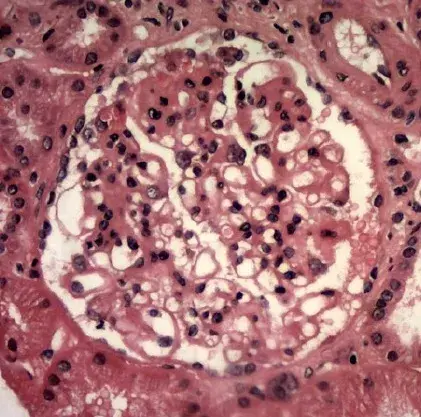

É possível identificar um glomérulo com quebra ruptura da MBG, com crescente celular no espaço de Bowman (seta branca), célula gigante multinucleada (estrela) e ruptura da cápsula de Bowman (seta preta) (PAS; 400×). PAS, ácido periódico-Schiff.

A biópsia renal revelou GN crescêntica necrotizante difusa sem hipercelularidade endocapilar. Alguns raros glomérulos continham células gigantes multinucleadas.

A avaliação da microscopia de luz pode ajudar na diferenciação de casos de **GN por anti-MBG** de casos **GN-ANCA**, já que na GN anti-MBG não observamos hipercelularidade endocapilar e pode ser identificado a presença de células gigantes multinucleadas, estas células gigantes multinucleadas resultam a natureza explosiva e a rápida destruição dos glomérulos observadas em anti-MBG

Desta forma, a presença de lesões crescentes temporalmente semelhantes e células gigantes multinucleadas na microscopia de luz (MO) pode ajudar no diagnóstico precoce.